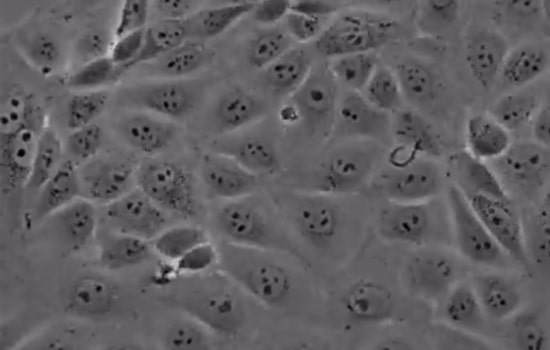

MDCK cell lines

Adherent mammalian cell lines such as MDCK which can be grown in serum-free medium are currently the most popular as compared to Vero and have been reported to induce higher hemagglutination inhibition (HI) and neutralizing antibody (NAb) titers than egg-based vaccine. Particularly, notable is that adherent MDCK outperform the suspension form by producing a more robust virus.

Other specific advantages of MDCK lines are enabling rapid replication of virus in 3-10 passages (10-30d) resulting in high-titer viruses with fewer mutations. The net result is a shortening of the lead time for Vaccine production. Influenza B is particularly suitable for propagation in these cell lines. The safety and immunogenicity of vaccines from MDCK lines have been well-documented.